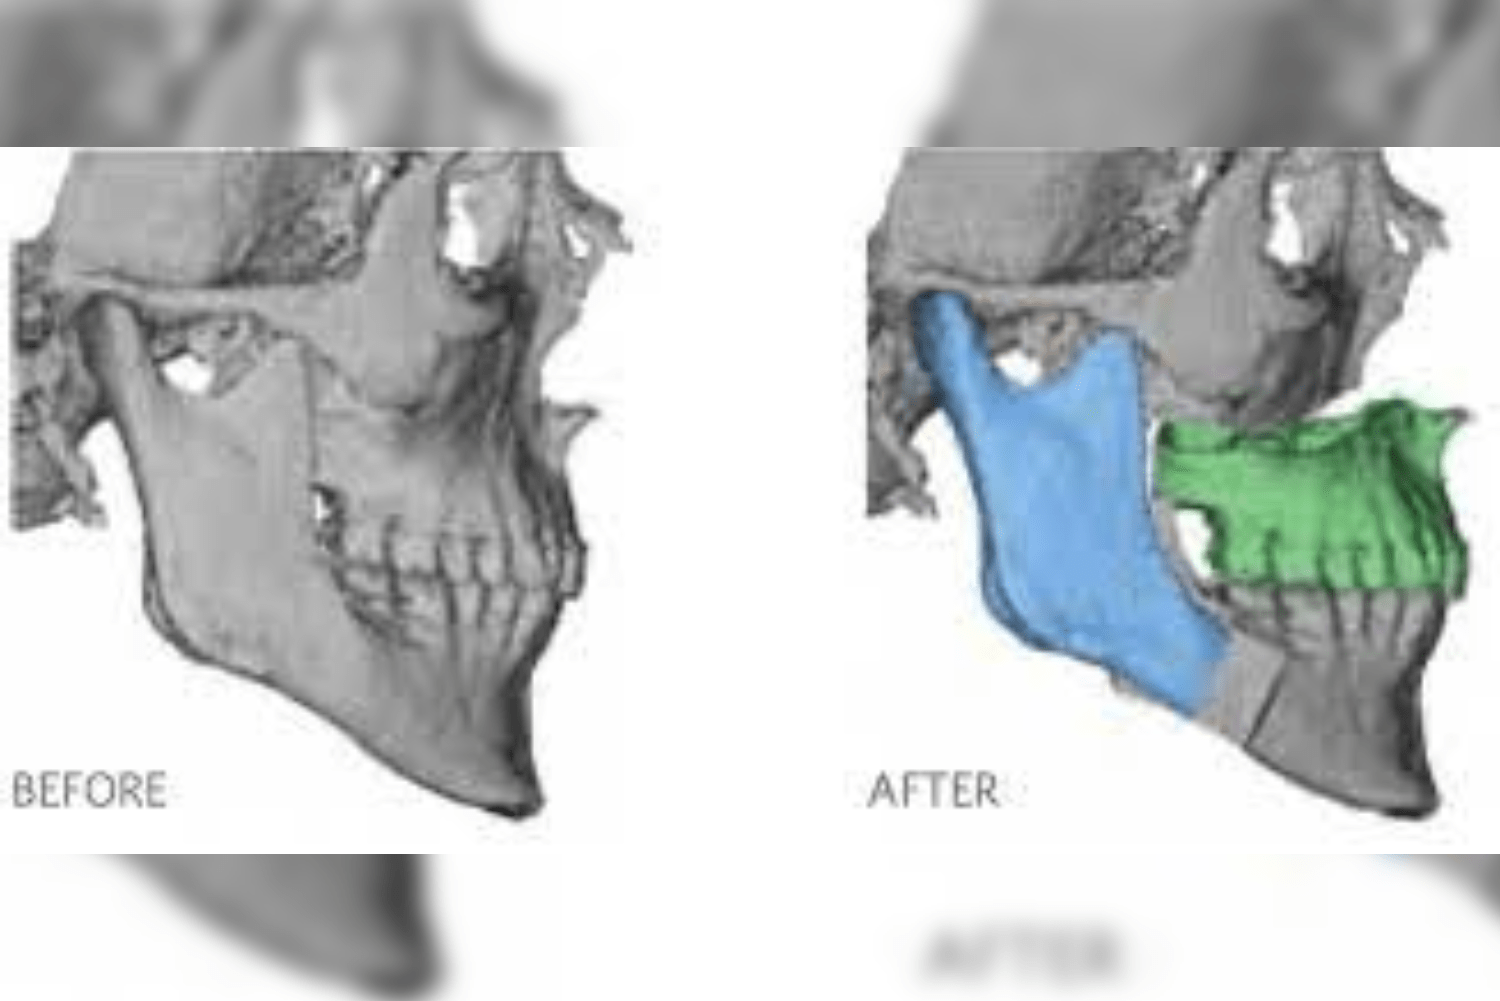

The second step is conversion of the imaging data into three dimensional digital models of the face.

Once the 3D reconstructed models are obtained, the surgeon and the engineers simulate the surgical steps on the model. The ankylotic mass is removed and the prosthetic components are positioned digitally in the desired position replicating normal anatomy.

Based on the virtual surgical planning, the patient-specific implants are customised. Along with these implants, surgical guides are fabricated to aid in surgical precision and improved surgical time.